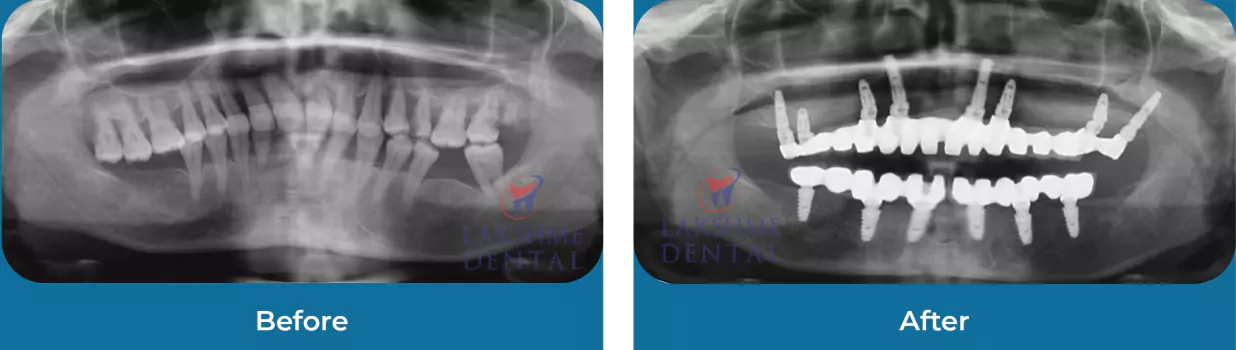

Implants

Full Mouth Rehabilitation